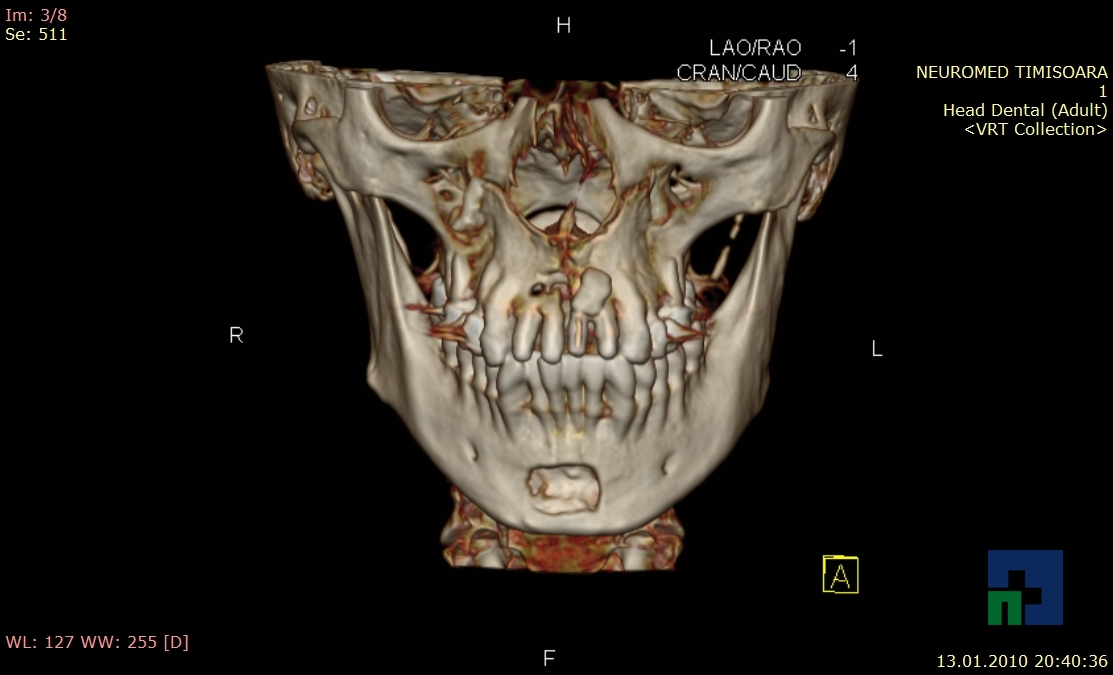

În cazul traumatismelor cranio-cerebrale:

- Diagnosticul traumatismelor de bază de craniu

- Diagnosticul fracturilor:

- Unice

- Multiple

- Cu înfundare

- Complexe cranio-sinusale

- Complexe cranio-etmoidale

- Complexe cranio-orbitare

- Complexe cranio-faciale